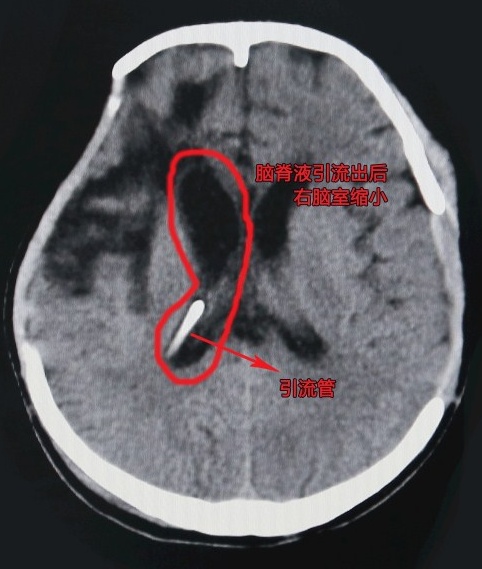

术后患者右脑室缩小,颅内压降低

侯主任查看病人颅脑CT后发现,病人脑积水有增多的迹象,若不尽快手术引流,会导致脑室增大进而影响病人伤情恢复。征求病人家属同意后,侯主任于11月13日下午为患者行脑室-腹腔分流术。